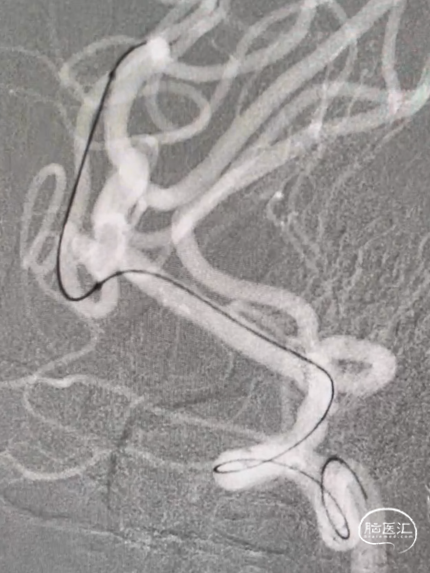

术后影像及随访

患者术后恢复良好,术后4天出院,出院mRS 0分。

术后3个月门诊随访,复查头颈部CTA:动脉瘤不显影,载瘤动脉通畅。

复查CTP未见明显异常。